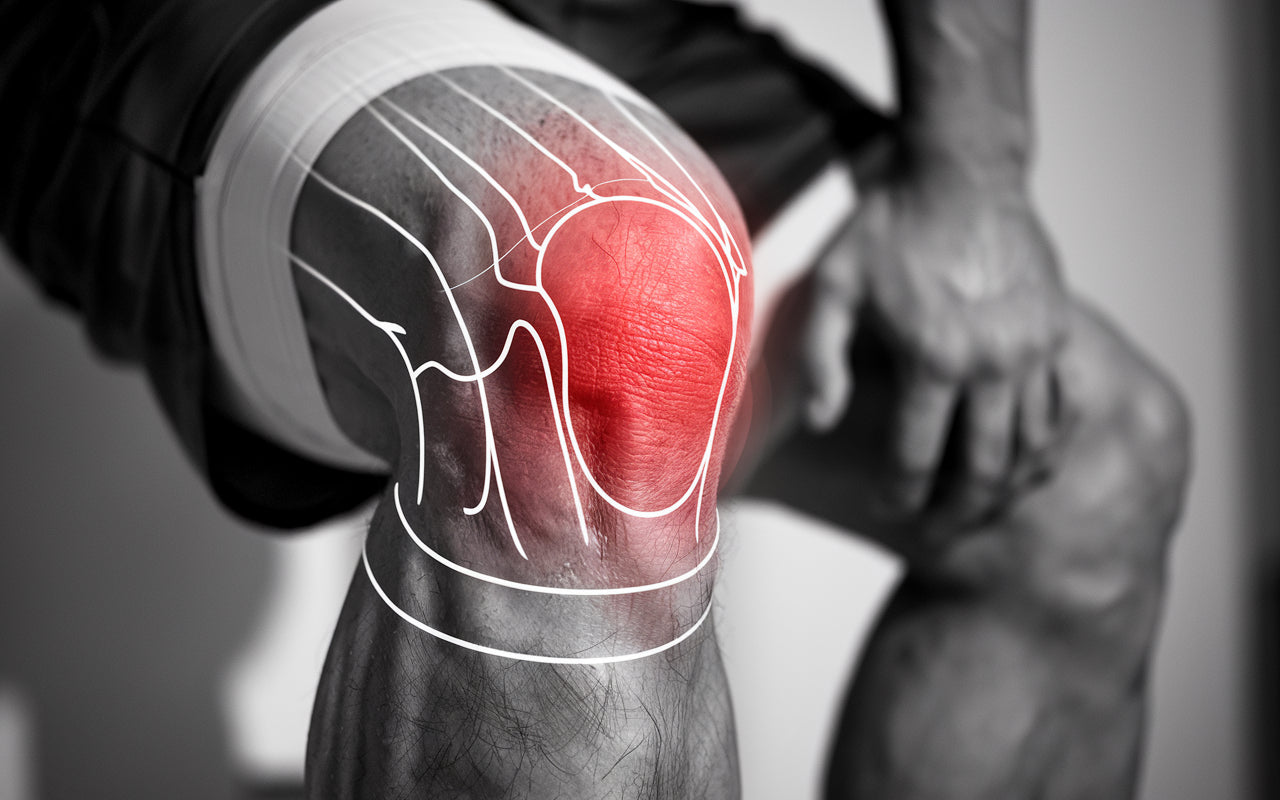

The knee joint is one of the most complex joints in the body and is subjected to great stress on a daily basis. Knee problems can affect people of all ages and arise for many different reasons.